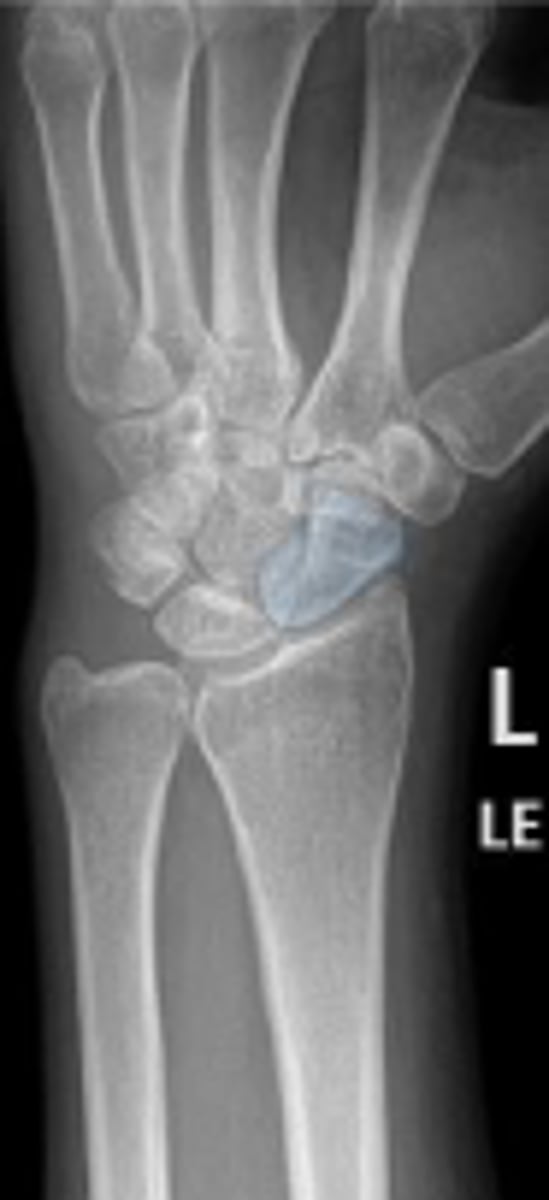

Left lunate

What is outlined?